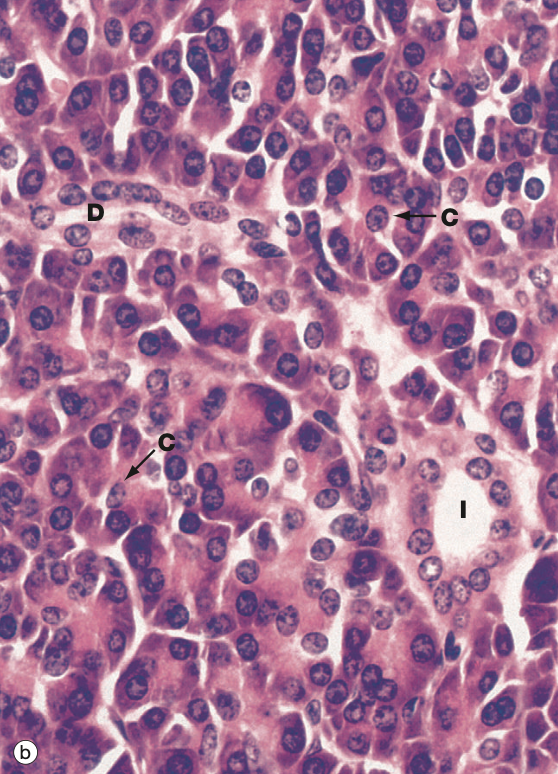

Identify the Organ and Structures?

Pancreas; (splotchy) islets of langerhans (lighter), acinar G (darker outside)

Pancreas; acinar G looks like flower

Pancreas; acinar/exocrine G (flower)

Harder for me…Pancreas; (splotchy) islets of langerhans (lighter), acinar G (darker outside)